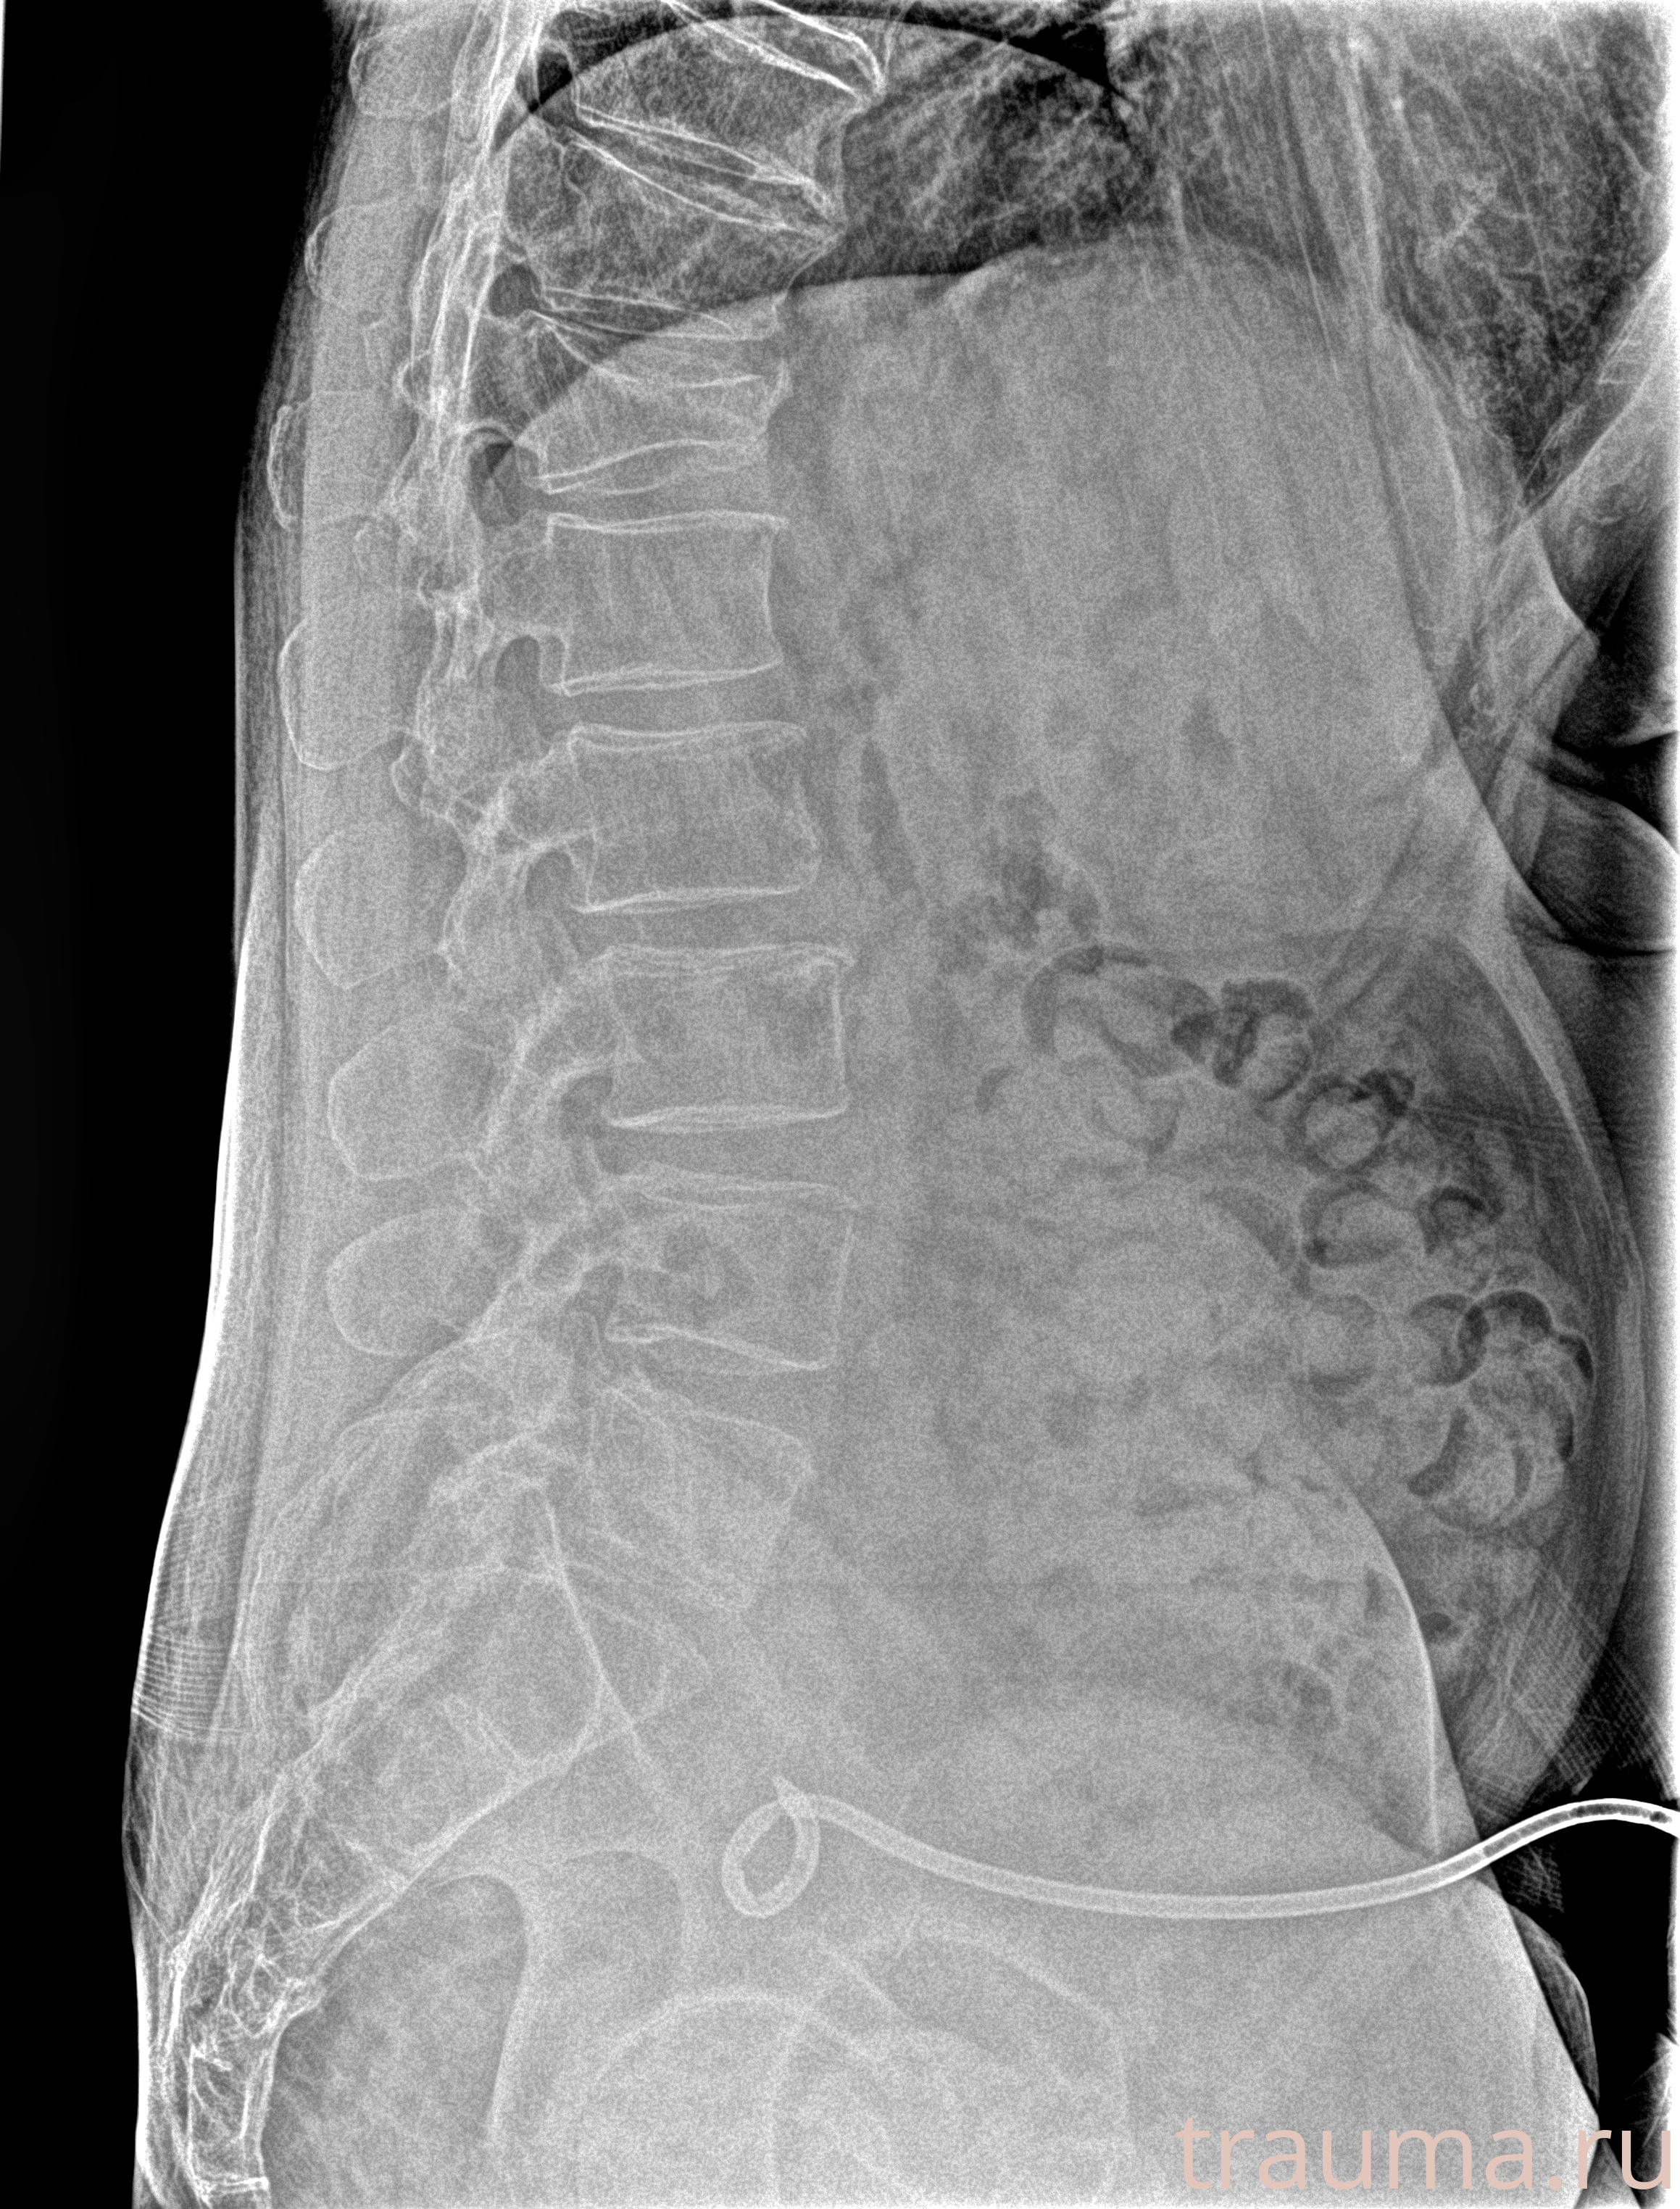

Рентгенограммы

Рентген на дому: по вашему адресу приезжает врач-рентгенолог, травматолог-ортопед с мобильным рентгеновским аппаратом, проводит диагностику травмы или заболевания, делает необходимые рентгенограммы, дает рекомендации по дальнейшему лечению. Получить качественные снимки в домашних условиях возможно благодаря уникальной методике, разработанной МосРентген Центром для института  Склифосовского